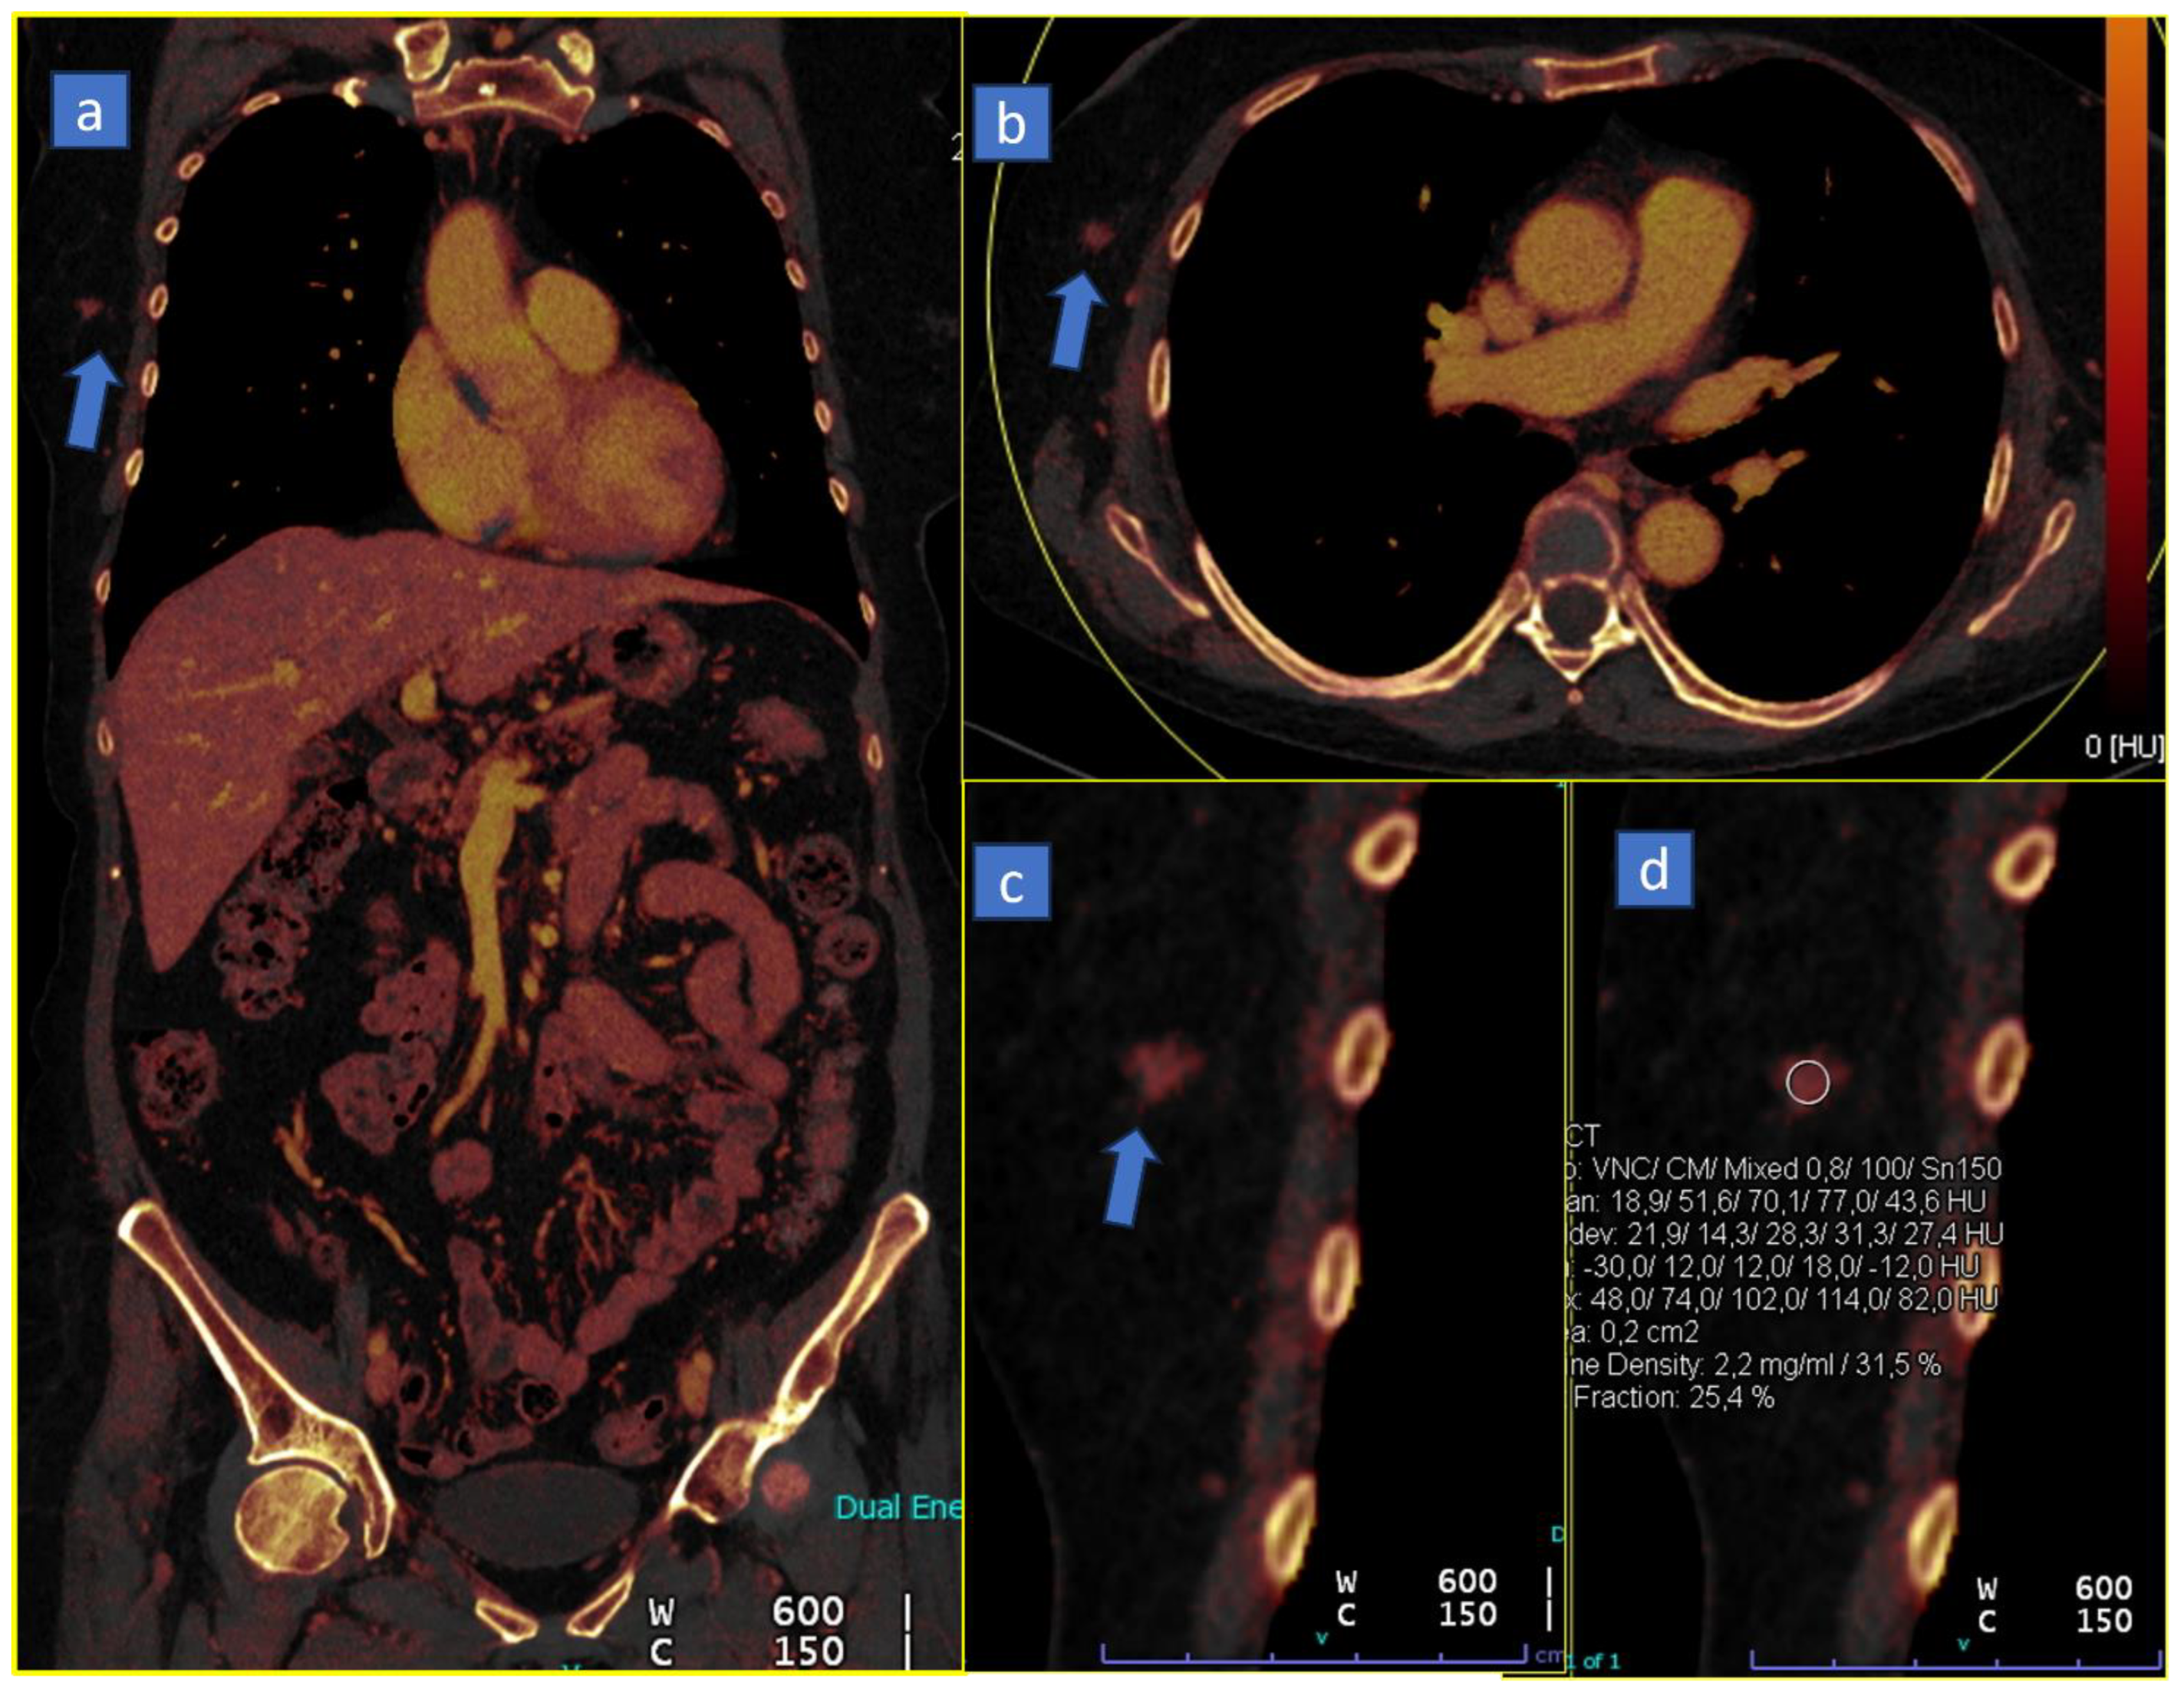

4. Virtual Monoenergetic

4.1. Better Conspicuity of Lesions